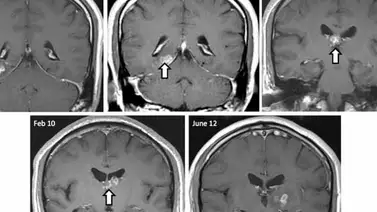

Una biopsia mostró la inflamación en el cerebro del hombre, pero no pudieron determinar la causa exacta de sus síntomas. Tras una biopsia final, los cirujanos desenterraron el origen de los problemas neurológicos del hombre: una solitaria que se había colado en el cerebro del paciente durante los últimos cuatro años.

El parásito había viajado más de 2 pulgadas de la parte derecha del cerebro a la parte izquierda, antes de ser eliminado con éxito a través de la cirugía. Ahora, el paciente está muy bien.